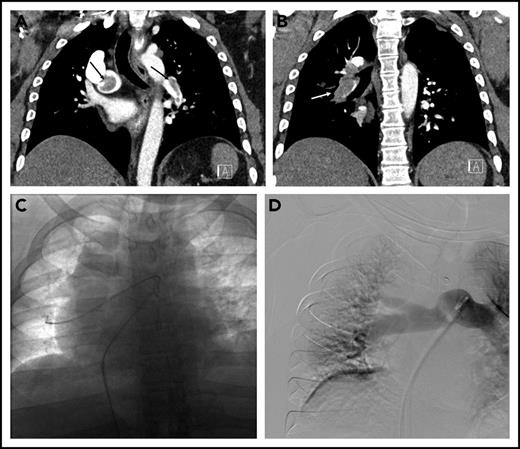

A 78-year-old woman with hypertension, hyperlipidemia, and chronic obstructive pulmonary disease presented to the emergency room with 4 hours of chest pain associated with lightheadedness and diaphoresis. She had an oxygen saturation of 86% on room air and a systolic blood pressure of 80 mmHg. Her oxygen saturation improved to 98% on 2 L of oxygen by nasal cannula. Initial labs were notable for a troponin of 0.44 ng/mL (normal <0.04 ng/mL). Electrocardiography was normal. The d-dimer was 8820 ng/mL, prompting CT angiography of the pulmonary arteries, which revealed multiple bilateral PE in the main pulmonary arteries (Figure 2A), with evidence of right heart dilation (Figure 2B) and strain on transthoracic echocardiography. The patient was started on UFH and transferred to the intensive care unit (ICU) for further management. Lower extremity ultrasound revealed residual acute DVT in the right popliteal and tibial veins. The PERT was activated, and the initial consensus was to not escalate therapy beyond anticoagulation because she had stabilized. However, 12 hours after admission to the ICU, she developed hypotension (systolic blood pressure of 78 mmHg) and was started on vasopressors. The PERT was alerted to this new development, and the decision was made to proceed with catheter-directed therapy.

Massive pulmonary embolism in patient 3. (A) Axial CT image demonstrating thrombus in the right and left main pulmonary arteries. (B) Axial CT image through the heart demonstrating an enlarged RV (dashed line) to LV (solid line) ratio. (C) Thrombus on pulmonary angiography (arrows), extending from the left main pulmonary artery into the left lower-lobe pulmonary artery. (D) Indigo aspiration device (arrow) within the left lower-lobe pulmonary artery. (E) Placement of bilateral CDT infusion catheters (arrows).

Because of the patient’s instability and hypoxia, general anesthesia with endotracheal intubation was performed by a cardiac anesthesiologist. Pulmonary angiography was performed, showing the bulk of the thrombus in the left lower-lobe pulmonary artery (Figure 2C). The Indigo CAT 8 aspiration device (Penumbra, Inc., Alameda, CA) was used in an attempt to rapidly debulk thrombus (Figure 2D). Bilateral multisidehole infusion catheters were then positioned in each pulmonary artery (Figure 2E), and 0.5 mg rt-PA/catheter/h was initiated, with UFH infusion targeted to PTT less than 2 times the institutional norm. Additionally, a retrievable inferior vena cava (IVC) filter was placed at the time of the procedure. After a total dose of 12 mg, the patient was noted to have significant oozing from the catheter site, so thrombolytic infusion was halted. Her blood pressure was normal, and she was no longer requiring vasopressor support. The catheters and sheaths were removed at the bedside. Therapeutic-level UFH was resumed. The patient was discharged 2 days later on anticoagulation. The IVC filter was removed percutaneously 6 weeks later, at which time the patient was doing well with no functional limitations.